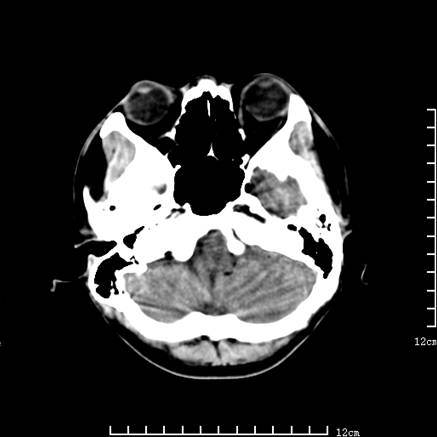

以下是引用jiajie在2008-9-5 22:25:00的发言:[br]男,22岁,头痛1月余。脑室、脑池内病变ct值约-120hu。[br][br]双侧侧脑室内低密度影充填,出现脑脊液脂肪平面,脑池内亦可见弥散分布的斑点状低密度影,脑室脑池未见明显扩大。[br]考虑胆脂瘤破裂后内容物进入脑脊液。